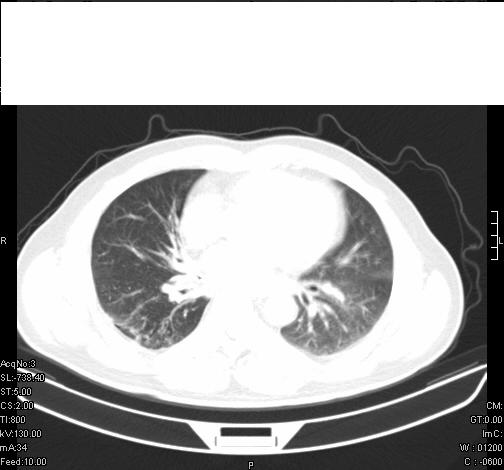

标题: CT6685:右肺阻塞性炎症,增强CT。

前几天,发了患者的平扫片,患者抗炎一周后增强扫描。右中叶病灶吸收明显,但下叶病灶未见明显吸收。右肺门可见结节影,看来凶多吉少

病灶在下叶,散发,抗炎治疗有效,考虑炎症,楼主说的肺门结节看的不明显

右肺下叶散在的斑片状致密影,下叶支气管变窄。考虑:右肺慢性炎症。

右下肺炎性改变

炎症是首选,不能排除肺癌

既然抗炎治疗有效,可继续治疗;右肺下叶支气管管腔狭窄,管壁增厚,右下肺见斑片状高密度影,右侧主支气管后见结节影(淋巴结?),肺癌不能排出。